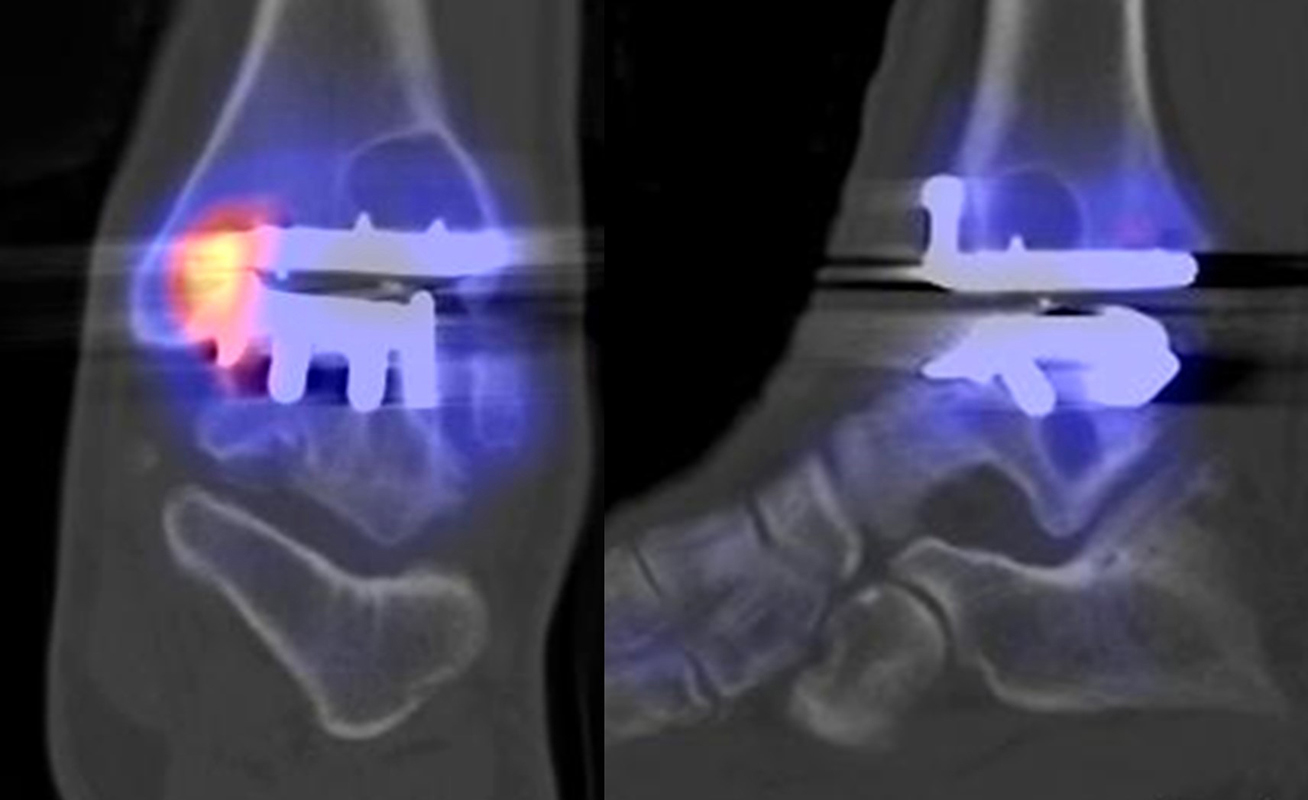

Beispiele für SPECT/CT-Untersuchungen nach OSG-TEP sind in den Abbildungen 6.1. bis 6.3. abgebildet.

Gurbani et al. evaluierten 37 Patienten mit schmerzhaften Sprunggelenkprothesen mit SPECT/CT und korrelierten die Ergebnisse mit klinischen und intraoperativen Befunden. Die SPECT/CT-Ergebnisse korrelierten zu 89,2 % (33/37 Pat.) mit der definitiven Diagnose. 28 Patienten wurden operativ revidiert und der Vergleich der SPECT/CT-Befunde mit den intraoperativen ergab eine Übereinstimmung von 92,9 % (26/28 Pat.). Die SPECT/CT identifizierte in den meisten Fällen aseptische Lockerungen (12/33 Pat.) und Impingement (11/33 Pat.). Seltenere Diagnosen waren Fehlstellungen (4/33 Pat.), Zystenbildungen (2/33 Pat.), subtalare Arthrosen (2/33 Pat.) und Infektionen (2/33 Pat.) 51.

Die Autoren beschreiben einen Fall, der neben einem Fokus am lateralen Malleolus auch eine starke flächige Anreicherung am talaren Prothesen-Knochen-Interface 17 Monate nach TEP-Implantation aufwies, so dass neben dem Verdacht auf ein laterales Impingement auch der Verdacht auf eine Lockerung der talaren Prothesenkomponente geäußert wurde. Intraoperativ bestätigte sich die Lockerung der talaren Prothesenkomponente nicht, sondern nur das laterale Impingement, welches mittels Debridement erfolgreich therapiert wurde 51. Da der Pat. bereits vor der TEP-Implantation eine Triple-Arthrodese erhalten hatte (welche im SPECT/CT unauffällig war), kann eine solche flächige Mehrspeicherung auch als weitgehend asymptomatische Stressreaktion gewertet werden.